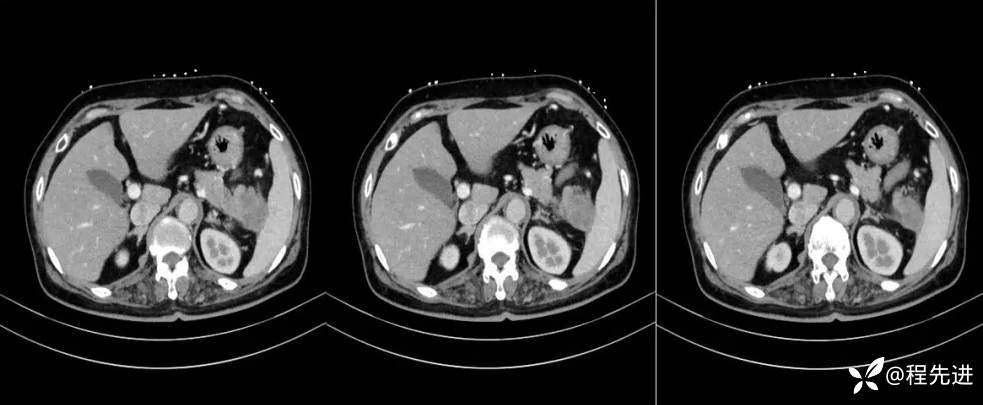

【现病史及既往史】:体检发现胰尾部肿块4年,当时手术病理提示异常增生性病变,现发现右侧顶部包块,逐渐增大,无明显感觉不适

影像检查: